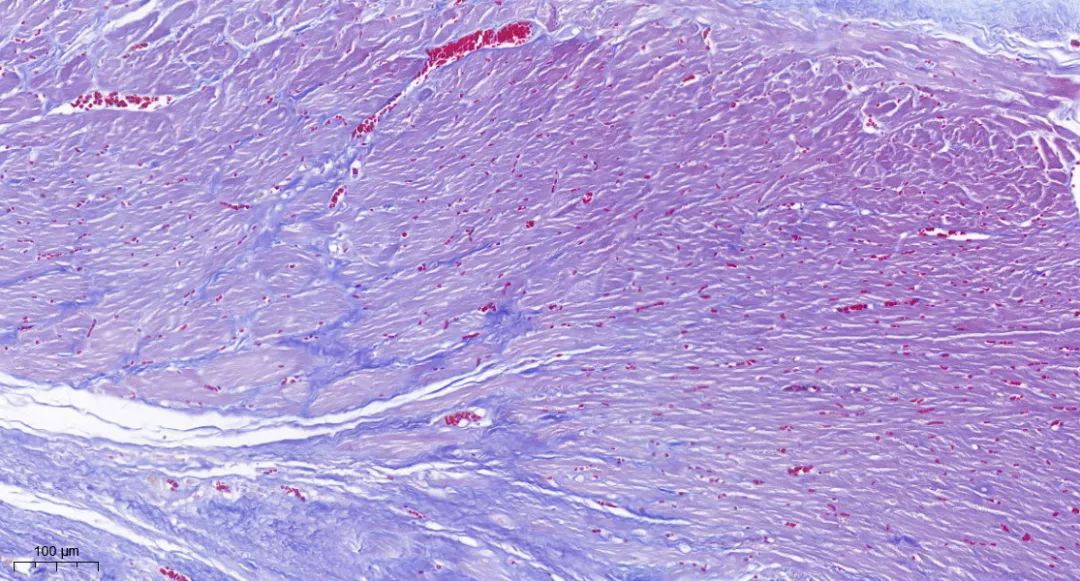

Masson染色

Masson染色,也称为马松染色,是一种广泛应用于观察组织纤维化的经典结缔组织染色方法。它通过特殊的染色步骤和染色剂,能够清晰地区分并显示组织中的胶原纤维和肌纤维,为研究人员提供了深入了解细胞和组织结构、形态及变化的重要工具。

其中,胶原纤维通常呈现为蓝色,而肌纤维则呈现为红色。

※实验结果示例:

胶原纤维通常呈现为蓝色,而肌纤维则呈现为红色。

masson染色·皮